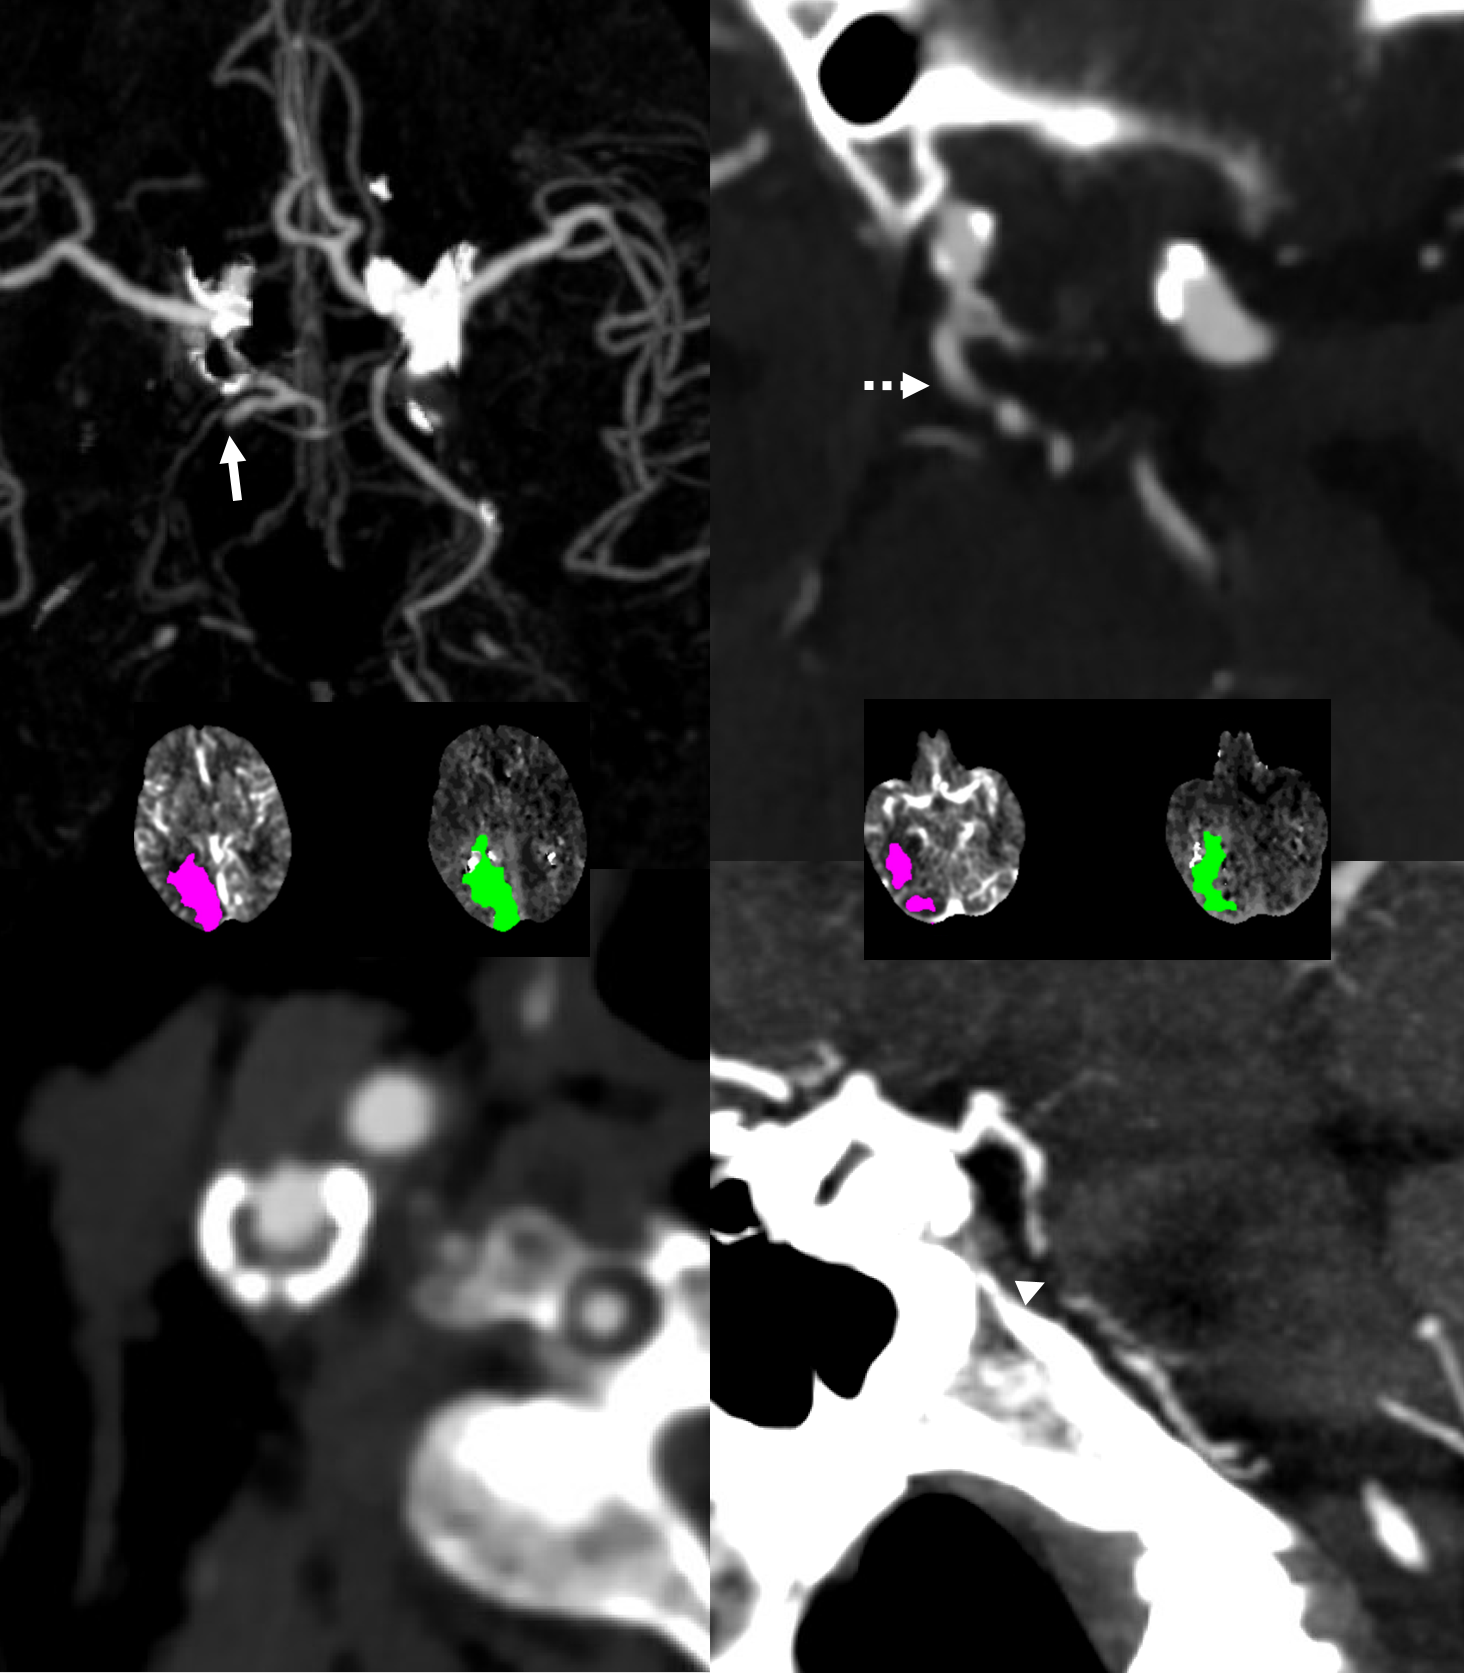

In this variant, the trigeminal artery (white arrow), supplies the lateral cerebellar territory classically belonging to the AICA In the Saltzman classification, this corresponds to Type IIIB

AP view of carotid injections showing the AICA (black arrow), with corresponding wedge-shaped void of its territory seen on the right vert injection. Notice fetal disposition of both PCOMs.

This variant can also be appreciated by an astute neuroradiologist on a CT angiogram